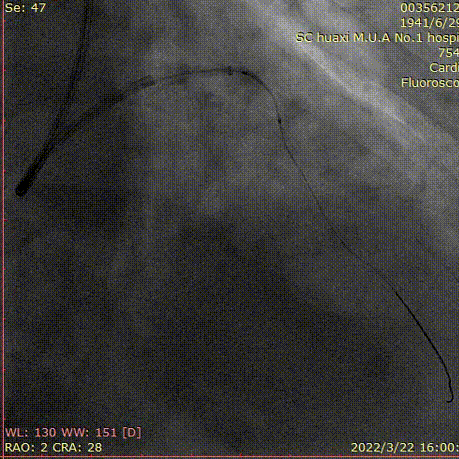

说明:高压球囊扩张后,支架仍无法通过,2.5预扩球囊锚定,送入Telescope™导引延长导管到前降支中远段。

说明:沿Telescope™导引延长导管输送支架。